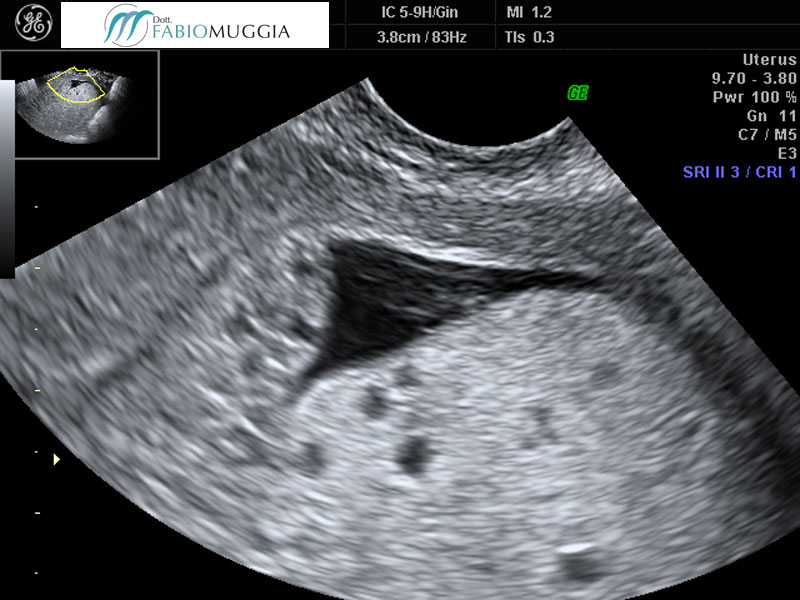

Biopsia ecoguidata di tessuto endometriale effettuata tramite curette di Novak. Si nota la grande sicurezza e precisione e la conseguente efficacia in virtu della continua osservazione ecografica.